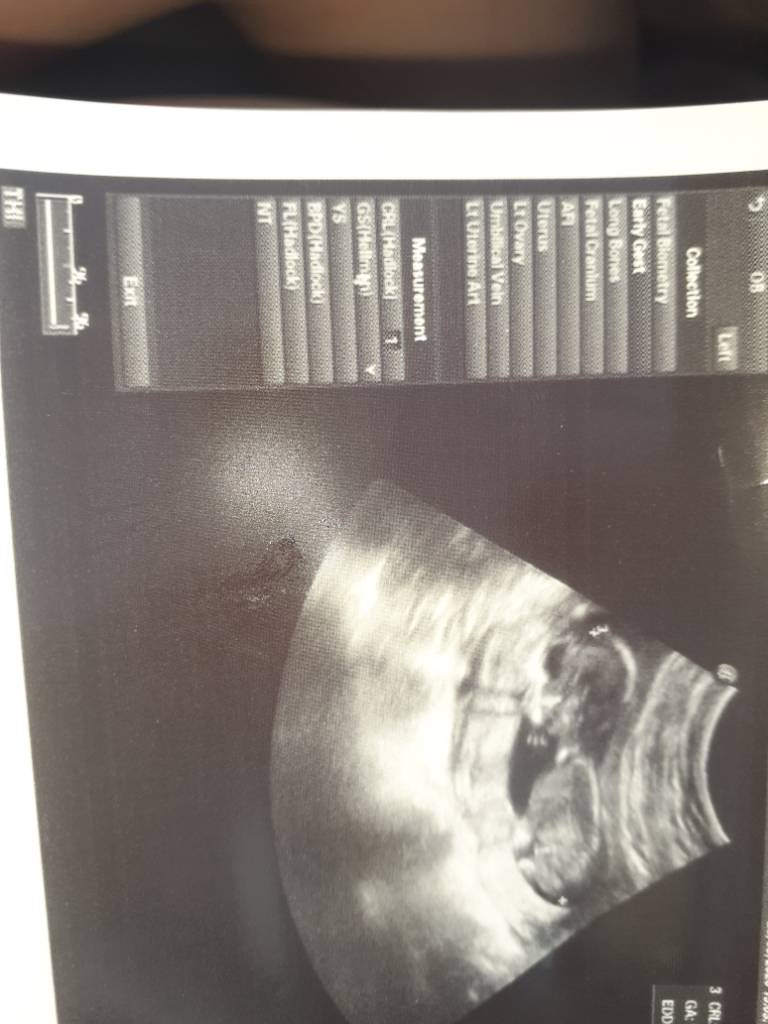

Ufff ZDROWIUTKIE!! KRWIAK SIE WCHŁONĄL!! płeć nieznana, łożysko nisko położone ale może się podnieść, no i dziwi mnie bo moje dzieci zawsze rosły wg terminu A ten wielkoludek minął termin z OM aż o tydzień :) zamiast 13+4 jest 14+4 [emoji33][emoji33]